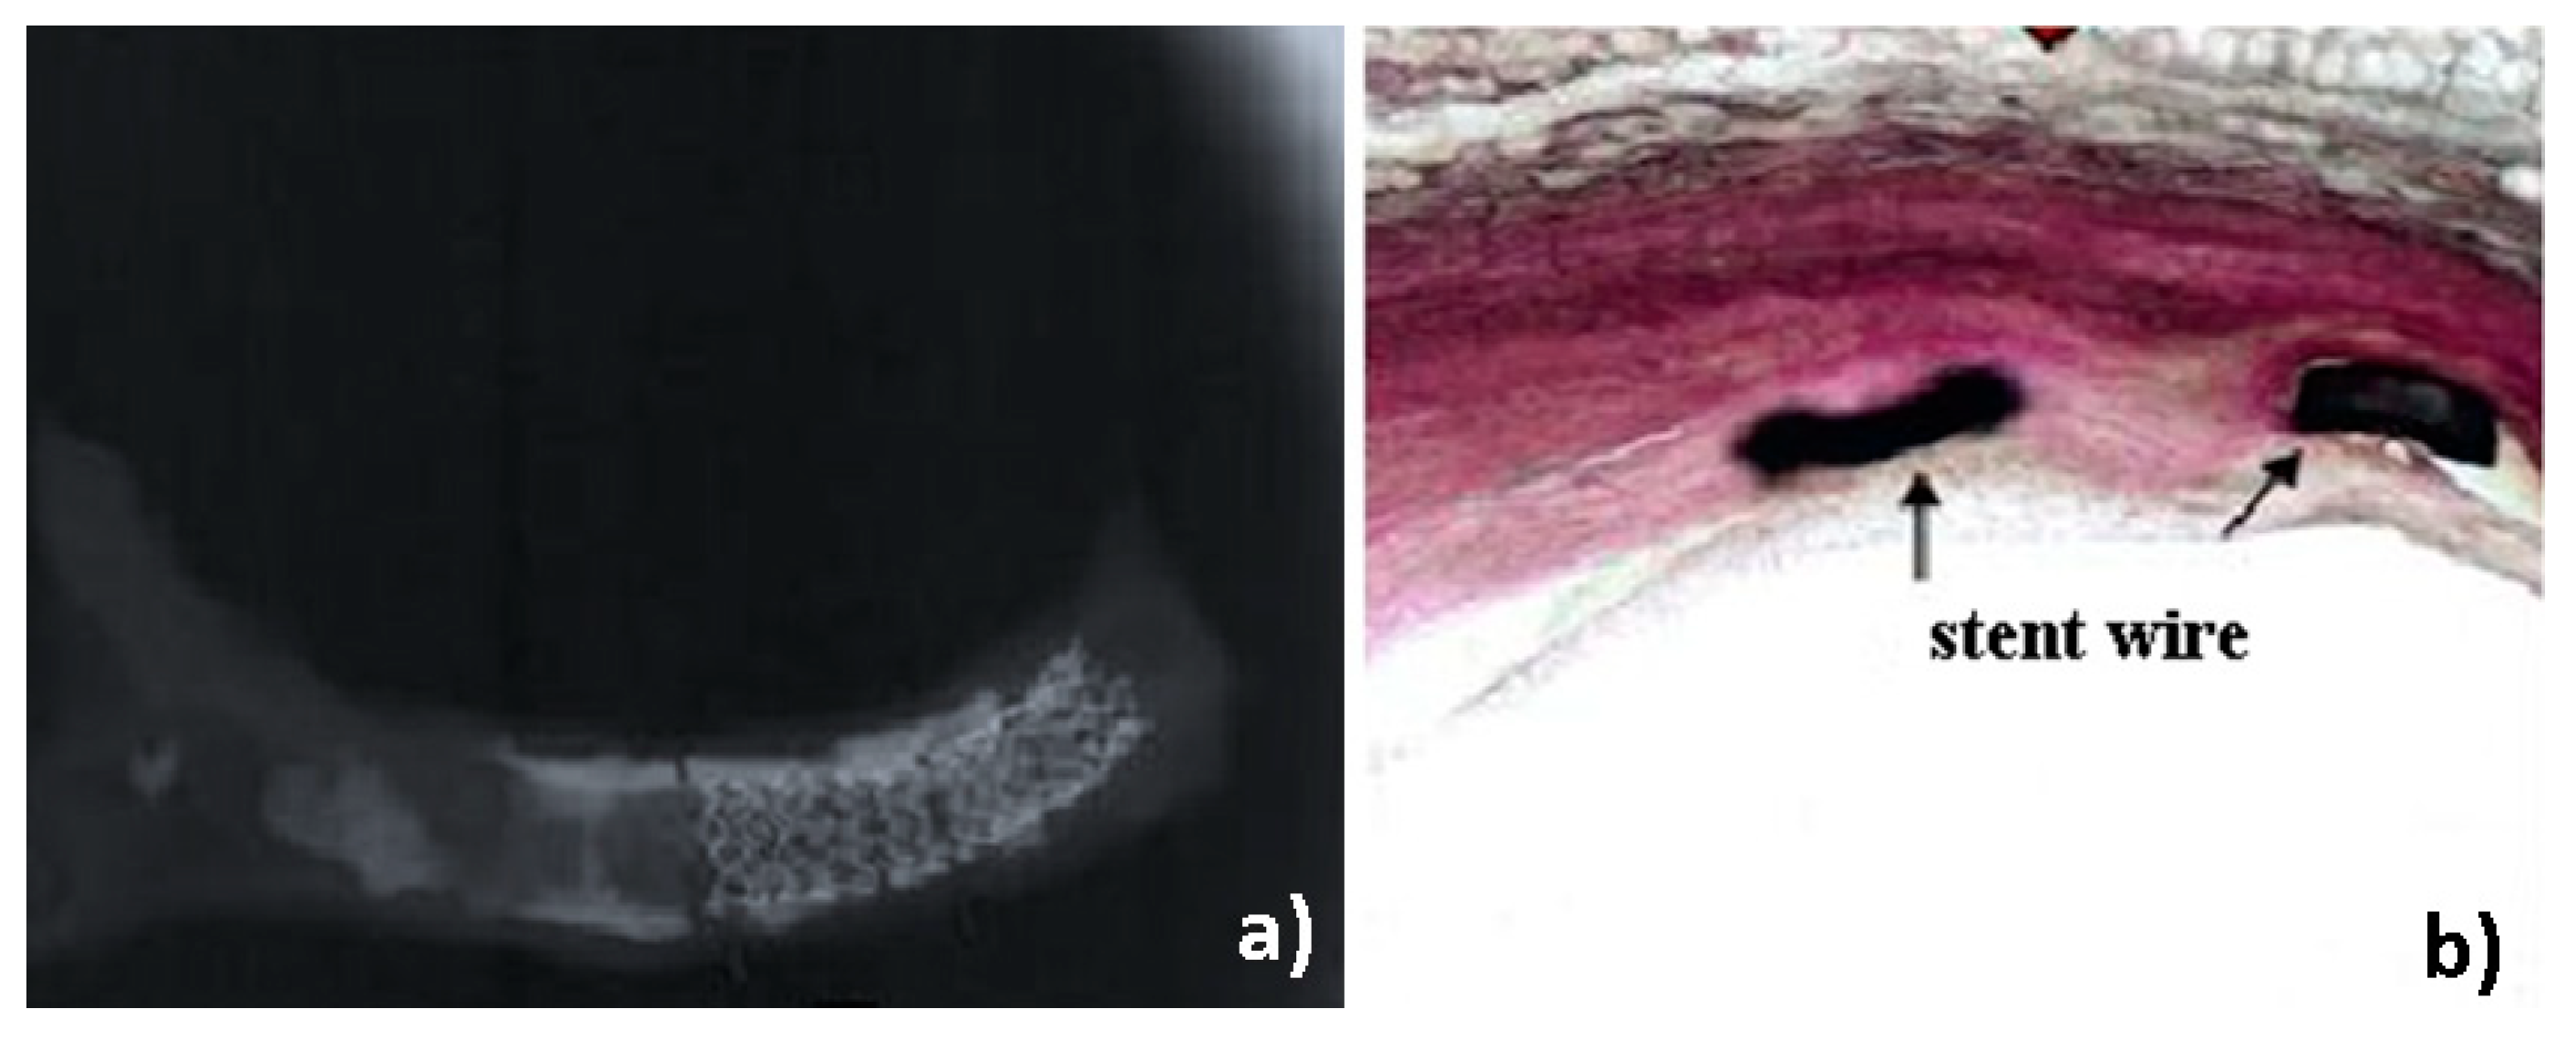

3.1. Post Exploratory Evaluation of Stents’ Surface by Light Microscopy

3.3. Evaluation of Tissue/Stents Interface by Histopathological Analysis of Surrounding Tissue